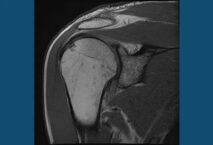

Thawing A Frozen Shoulder…with acupuncture

Medscape Clinical Essentials recently published an article called Thawing A Frozen Shoulder. Lots of treatment ideas were presented, from surgery to physical therapy, but absolutely no mention of using acupuncture or dry needling as a treatment option. Acupuncture Canada faculty member Irene Biemann, PT, CAFCI, corrects their oversight. In her article, following, Irene considers treatment Read More